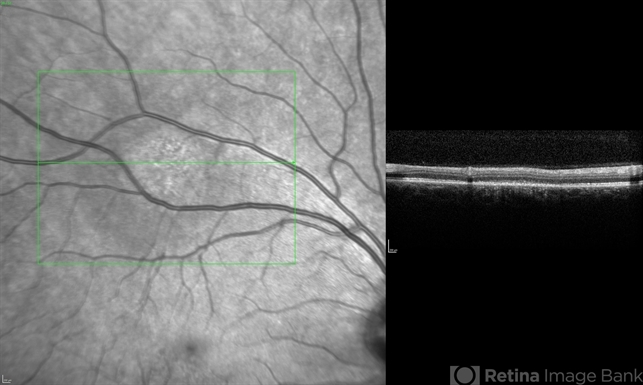

- Unilateral Acute Idiopathic Maculopathy

- chorioretinal inflammations, unilateral acute idiopathic maculopathy, Coxsackie

Optical coherence tomography system

Heidelberg Spectralis - Description

- Image on right shows infrared photo of the lesion of interest. SDOCT (image on left) through the lesion of interest shows hyperreflectivity of the RPE with disruption/loss of detail of the IS/OS junction.